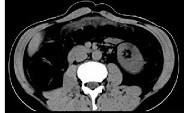

- 单项选择题女,51岁, 腹胀、腹痛、进行性消瘦,影像检查如下图, 最佳诊断是 ( )

A、乙状结肠Crohn病

B、乙状结肠结核

C、乙状结肠癌

D、乙状结肠淋巴瘤

E、乙状结肠息肉